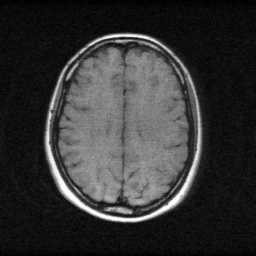

Reconstruction Gallery — 4 Scenes × 3 Scenarios

Method: CPU_baseline | Mismatch: nominal (nominal=True, perturbed=False)

Mean PSNR Across All Scenes

Per-scene PSNR breakdown (4 scenes)

| Scene | I (PSNR) | I (SSIM) | II (PSNR) | II (SSIM) | III (PSNR) | III (SSIM) |

|---|---|---|---|---|---|---|

| scene_00 | 16.369188751529634 | 0.3769596313670564 | 28.91599361455386 | 0.8937325593738555 | 43.0888232643681 | 0.9970601105022431 |

| scene_01 | 17.02984109629589 | 0.5076141905187631 | 29.54697836453365 | 0.9088858192167282 | 44.00498178524224 | 0.9974331602373123 |

| scene_02 | 19.876634796830935 | 0.5132084125883123 | 29.296469693787934 | 0.8901788054246903 | 45.80916505985154 | 0.9983439806976319 |

| scene_03 | 16.209230008064964 | 0.3451008090497886 | 28.211197909256423 | 0.8836538261470794 | 42.81516446798818 | 0.997371546825409 |

| Mean | 17.371223663180356 | 0.4357207608809801 | 28.99265989553297 | 0.8941127525405883 | 43.929533644362515 | 0.9975521995656491 |